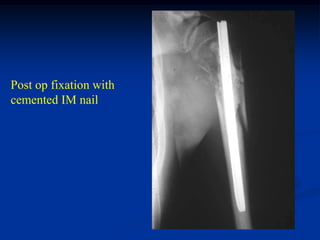

27 year male with path

fracture thru metastatic

melanoma from thigh

skin where he had a

resection 4 yrs ago

Black pigmentation in biopsy specimen

Post op fixation with

cemented IM nail